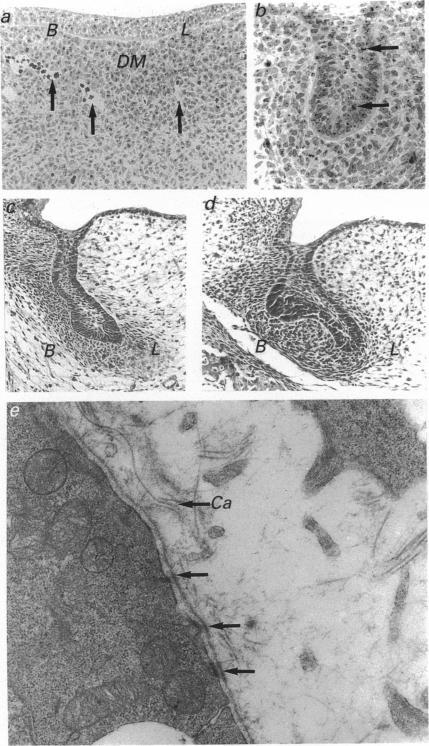

The lamina of the first mandibular molar teeth of rats, age range 13 d intrauterine (i.u.) to 16 d postnatal (p.n.), was examined by light and transmission electron microscopy to establish histological baselines of its development and fate. All material was obtained from animals anaesthetised with ether, killed by cervical dislocation and prepared by routine methods for both types of examination. Contrary to earlier reports that the lamina remains intact throughout development, mesenchymal elements disrupt the lamina. These were seen first at 19 d i.u., as collagen-filled bays in the basal epithelial layers, associated with partial loss of related basal lamina. In the early stages, collagen deposition was limited and it was not obviously preceded by epithelial cell death or transformation, even though many bay-related cells showed lipid and glycogen accumulations. Later disruption of the lamina showed more mesenchymal cells as well as collagen in deeper spaces. After the onset of tooth eruption, mesenchymal cells external to and within the lamina contained lysosomal bodies and these plus evidence of related epithelial cell death and capillaries in the laminar spaces became more and more apparent. Similar collagen deposits were observed in a successional tooth primordium, which appeared at term but eventually aborted between days 5 and 10 p.n. Thus disruption of the lamina by connective tissue began earlier than has been reported previously and progressed as the tooth erupted towards the oral cavity. The evidence suggests that this disruption is initiated and sustained by mesenchymal cell activity rather than by programmed cell death or transformation of the epithelium.

对年龄范围为子宫内13天至出生后16天的大鼠第一下颌磨牙牙板进行了光镜和透射电镜检查,以建立其发育和命运的组织学基线。所有材料均取自用乙醚麻醉、经颈椎脱臼处死的动物,并通过常规方法制备用于两种类型的检查。与早期报道称牙板在整个发育过程中保持完整相反,间充质成分会破坏牙板。这些最早在子宫内19天时可见,表现为基底上皮层中充满胶原的凹陷,伴有相关基底膜的部分缺失。在早期阶段,胶原沉积有限,且在其之前并没有明显的上皮细胞死亡或转化,尽管许多与凹陷相关的细胞显示出脂质和糖原积累。牙板后期的破坏显示在更深的间隙中有更多的间充质细胞以及胶原。在牙齿萌出开始后,牙板外部和内部的间充质细胞含有溶酶体,这些以及层状间隙中相关上皮细胞死亡和毛细血管的证据变得越来越明显。在一个相继牙胚中观察到类似的胶原沉积,该牙胚足月出现,但最终在出生后第5天至第10天之间退化。因此,结缔组织对牙板的破坏比以前报道的要早开始,并随着牙齿向口腔萌出而进展。证据表明,这种破坏是由间充质细胞活性引发和维持的,而不是由上皮细胞的程序性死亡或转化引起的。